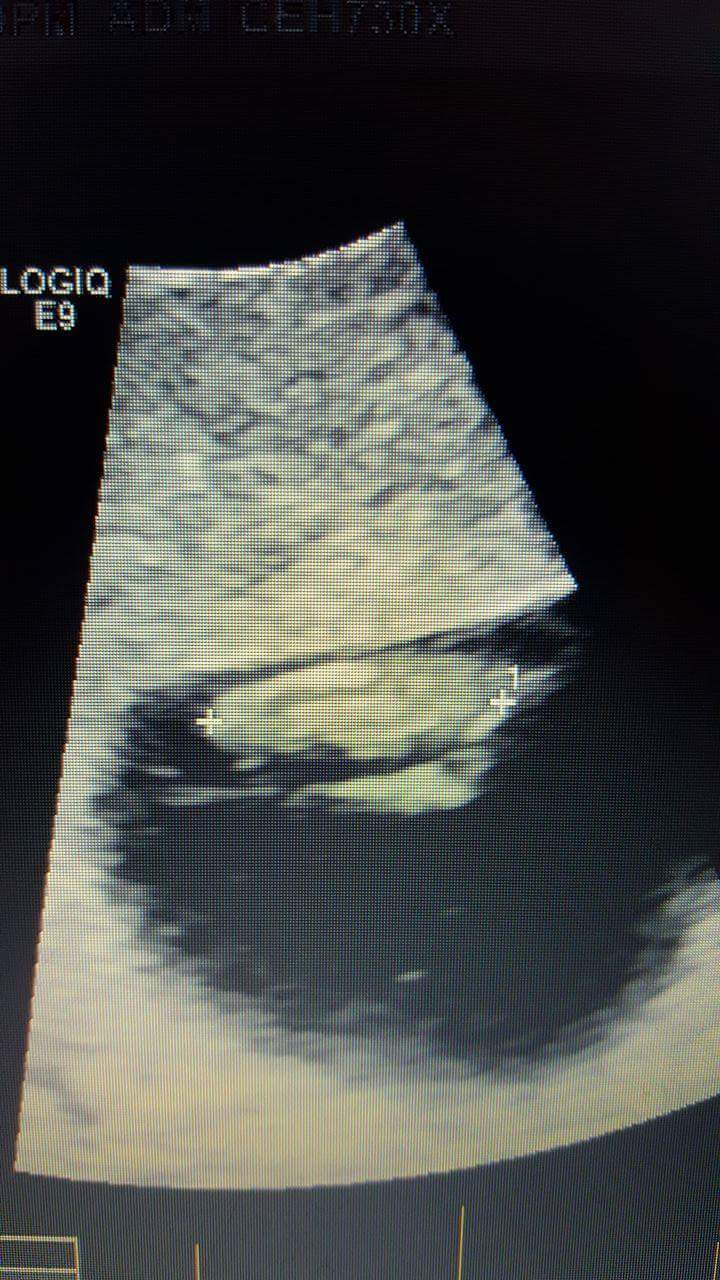

3rd,4th,5th and 6th are 12 week shots